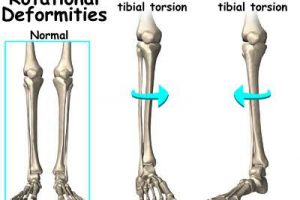

基本的な動きは曲げ伸ばしを行い、それに伴い回旋動作が入ります。

また膝の曲げ伸ばしの際には必ず軸運動が発生します。

この軸運動があることにより、曲げ伸ばしがきちんとできると言い換えることもできます。

少し複雑な図になりますが、膝の曲げ伸ばしをする時の軸は「X」です。

この軸が平行に保つことができれば曲げ伸ばしもスムーズなのですが、ガニ股のような形をした脚ですと軸が外側にずれてしまいます。